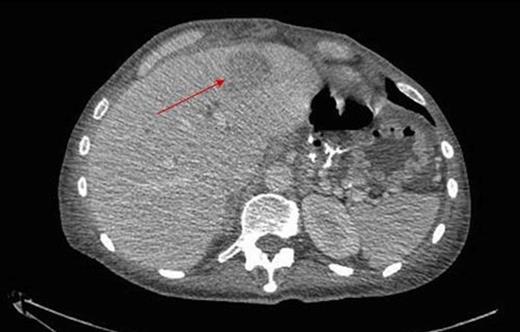

During inpatient stay, she became haemodynamically unstable with spiking temperatures and an elevating white cell count. She also complained of bilateral discolouration of her toes and examination revealed increasing oedema with diminished pedal pulses. A contrast CT scan of the abdomen confirmed ongoing collections with evidence of an aortic thrombus extending into the left iliac artery, presumed to be the embolic source for her vascular findings (figure 2 & 3). She underwent a further laparotomy and washout, and was heparinised postoperatively. There was resolution of vascular symptoms and evidence of improvement in peripheral perfusion postoperatively, and the patient was eventually discharged.

Extension into the left iliac artery shown by a filling defect (red arrow)